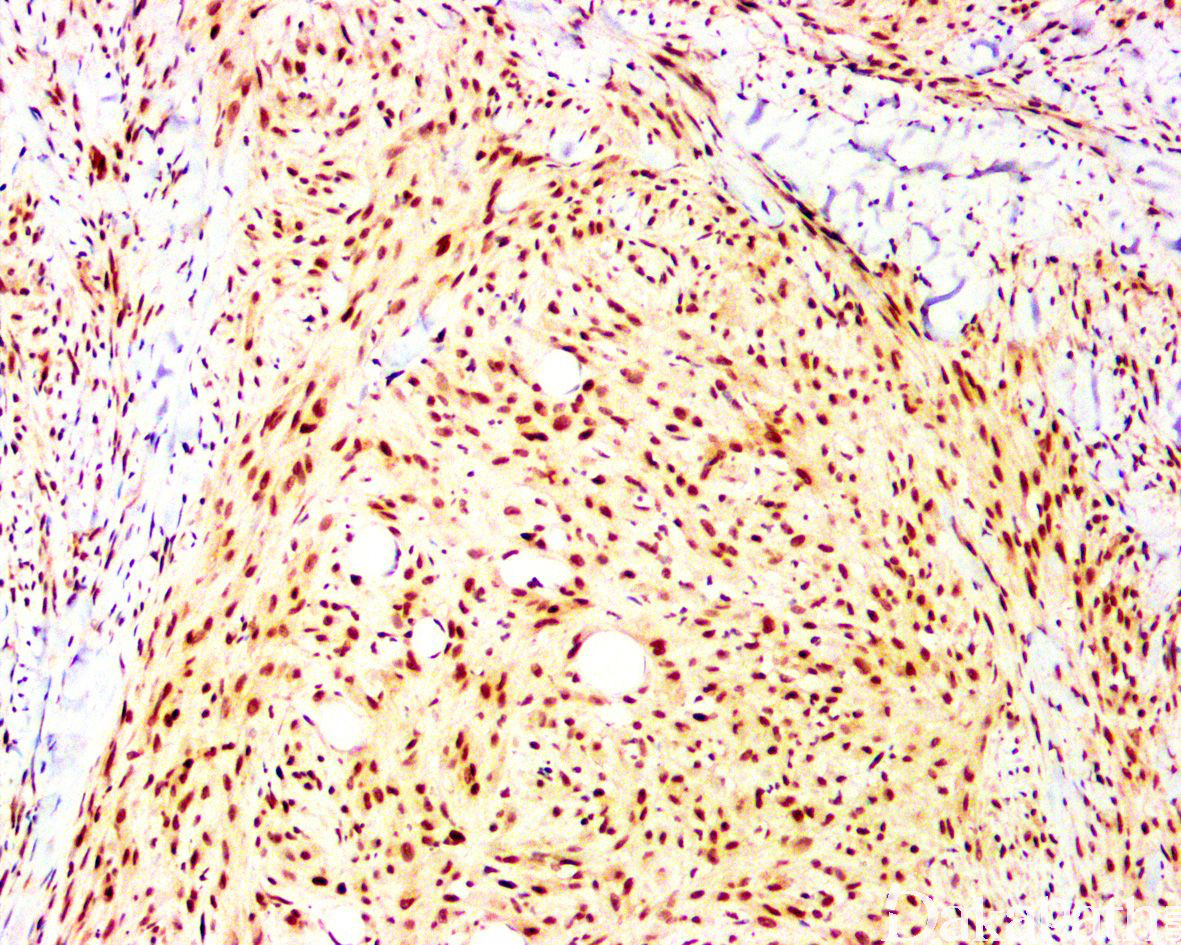

免疫组织化学染色:

肿瘤细胞恒定表达 FOSB、AE1/AE3. ERG、FLI-1. INI1,CD31 表达不一,较少表达 EMA,部分表达 SMA,而 CD34. Desmin、MyoD1. S100 阴性,INI-1 无表达缺失